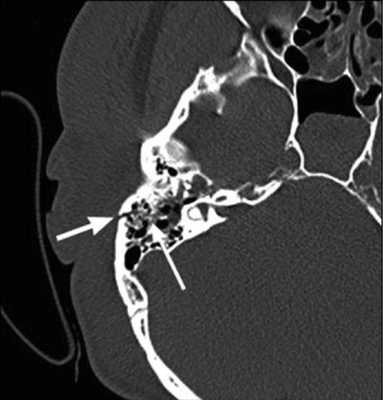

На КТ-снимке виден перелом пирамиды височной кости (указан стрелками)

Что покажет КТ височных костей

Во время КТ получают послойные снимки височной кости и окружающих тканей в трех плоскостях. Толщина среза составляет всего несколько миллиметров, что позволяет врачу-рентгенологу рассмотреть не только все анатомические образования, но и минимальные патологические изменения.

С помощью КТ височных костей можно выявить любые заболевания воспалительного, травматического, опухолевого характера. Метод применяется для диагностики следующих патологий: